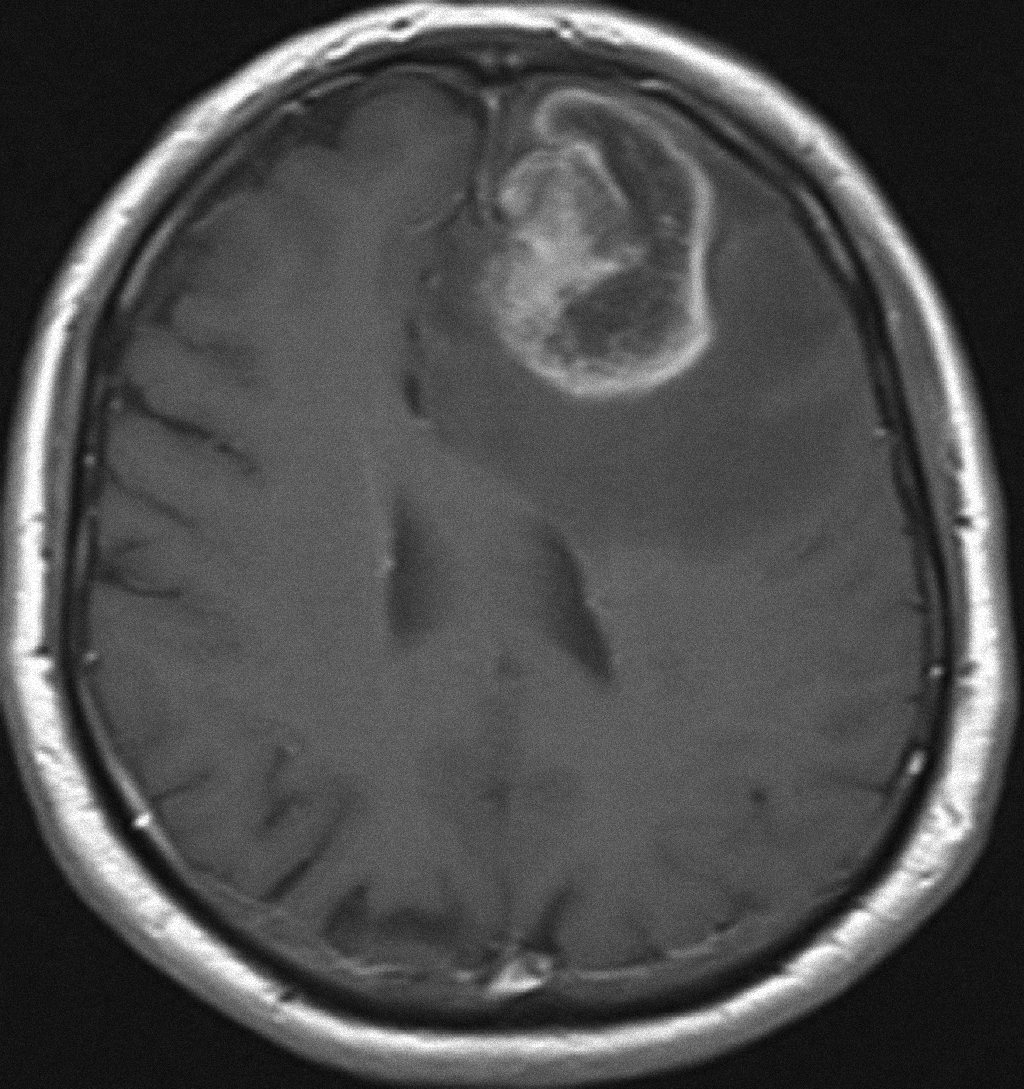

La paciente inicia tratamiento con dexametasona 4 mg cada 8 horas e ingresa en el Servicio de Medicina Interna para completar estudios. La analítica muestra un descenso de la cifra de plaquetas, una anemia leve sin valores alterados en la bioquímica. La imagen de resonancia magnética nuclear (RMN) cerebral muestra una lesión compatible con un glioblastoma multiforme izquierdo (Figura 1). El diagnóstico patológico fue de glioblastoma multiforme sin mutación detectada en IDH1 [1] por inmunohistoquímica, promotor del gen de la O6-methylguanine DNA methyltransferase (MGMT) metilado (predictivo de mejor respuesta terapéutica a agentes alquilantes) y compatible con el subtipo molecular clásico [2].